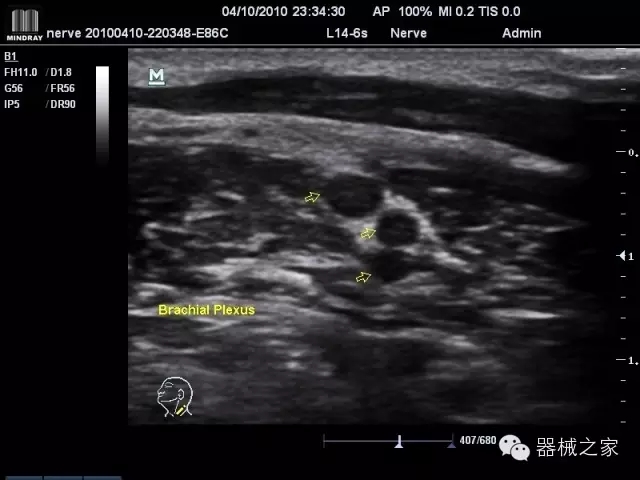

臨床圖片賞析

產品特點

·優(yōu)秀的圖像效果、強大的功能體驗、豐富的探頭選擇、合理的便攜式設計,全中文顯示及病人管理界面,使得M7在任何場合、任何時候都能快速響應更好的心血管、腹部、婦產、小器官等常規(guī)超聲檢查以及肌骨、神經、顱腦、術中等新興領域的使用需求;